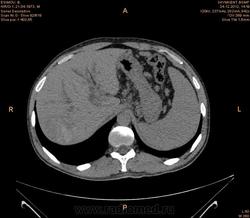

Предварительно образование головки ПЖ, и в печени. Что с ферментами?

на операций рак головки подж.железы с метастазир. печень.

инфильтрация тут нисходящей 12 перст кишки , расширенного холедох,расширенный вирсунгов проток ,нижная граница очень близко прилежит к нижней полой вене с правой почечной веной ,но четко визуализирутся передний листок фасции Героты(нельзя исключить ее инфильтрацию), инфильтрация конгломератом увеличенных лимфатических узлов ворот печени портальной вены с варикозным расширением вен, на вышележащий срезах четко определяются верхняя брыжеечная вена и артерия ,не хватает срезов для полной визуализации(помогли бы мпр),инфильтрирована восходящая ободочная кишка,конгломерат лимфат узлов за головкой поджелудочной железы в виде гиподенсивного участка вытянутой формы , ,мтс в печень,парааортальные